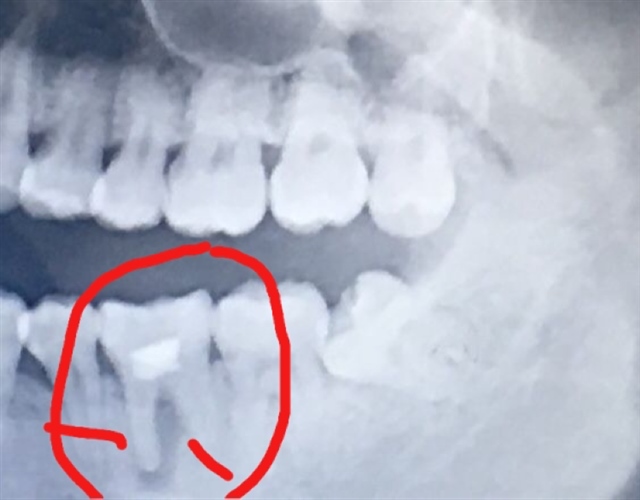

确实很恐怖,牙神经会拔掉